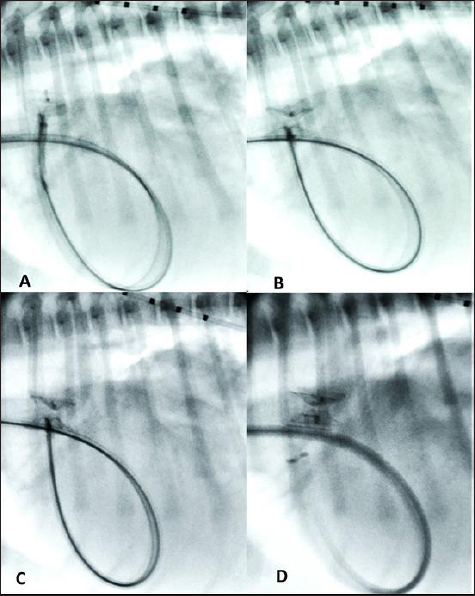

Thoracic radiographs showed left-sided cardiomegaly and pulmonary over circulation (Fig. 1). A transthoracic echocardiogram revealed severe left atrial and left ventricular dilation: left atrium/aorta (LA:Ao): 2.04, reference value: <1.6, normalized left ventricular internal diastolic diameter (LVIDDN): 3.02, reference value: ≤1.7) and large PDA, with an approximate minimal ostium and ampulla diameters of 5.2 and 10.3 mm (Fig. 2). Doppler echocardiography confirmed left-to-right flow across the PDA with a pressure gradient of 102 mmHg in systole and 41 mmHg in diastole. Mild mitral regurgitation was also noted.

Fig. 2. Transthoracic echocardiographic (right parasternal short axis view, optimized for duct visualization). (A) PDA visualization and its measurement and (B) left to right flow on CFM Doppler (dual mode).

Fig. 3. (A) Fluoroscopic sequence after the AVP II first disc has been released engaging the aortic side of the PDA and the central part left unsheated and (B) subsequently the other second component has been deployed an immediate “pull-through” into the pulmonary artery occurred immediately after to deployment of the whole device